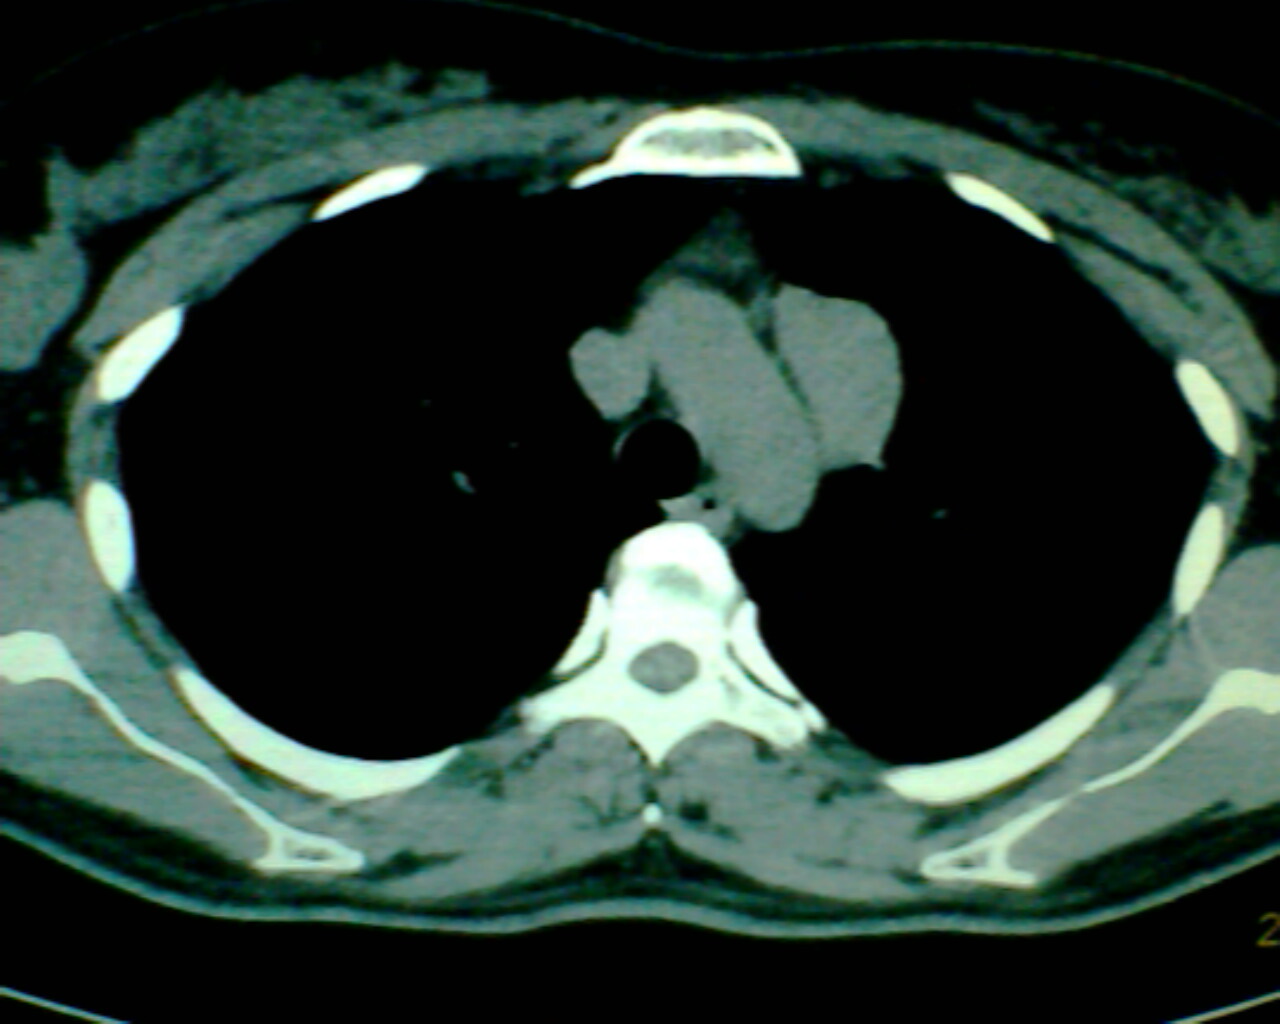

以下是引用狙击手在2007-4-10 22:46:00的发言:[br]考虑:左上纵膈旁型肺癌。理由:1,肿块与纵隔间有分隔;2,肿块呈分叶状;3,肿块突出面圆心在肺内;4,纵隔左移;5,纵隔内器官未见受压征象。